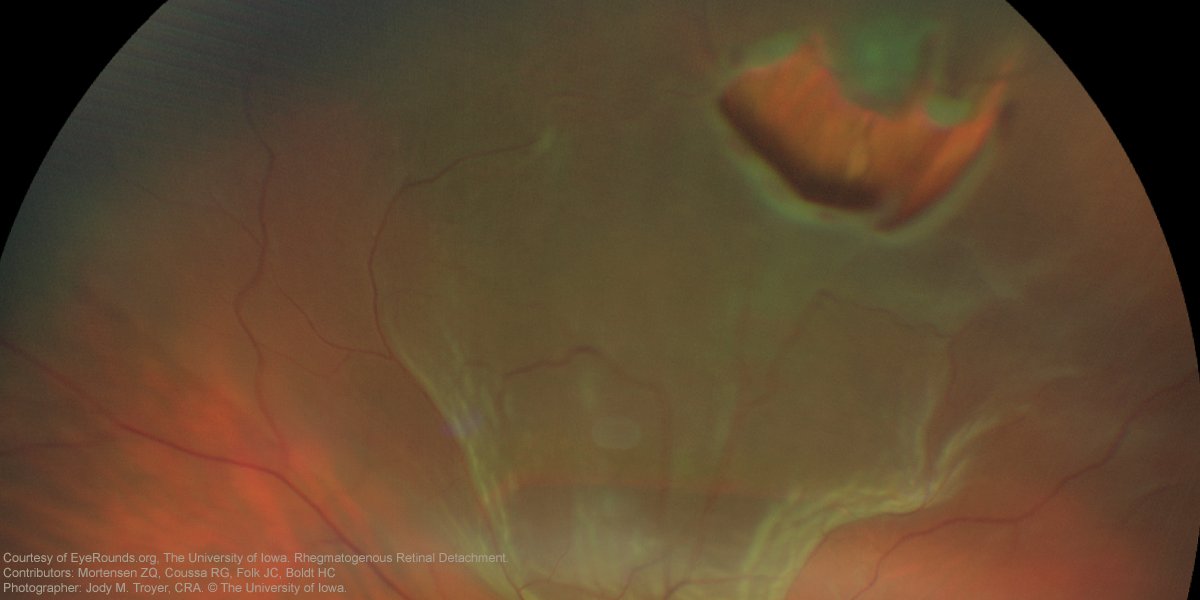

Did you know that the great English poet John Milton likely lost his vision due to bilateral #retinal detachments? Learn about this potentially devastating disease. #aao #ophthalmology https://t.co/SSvZdDEVtN